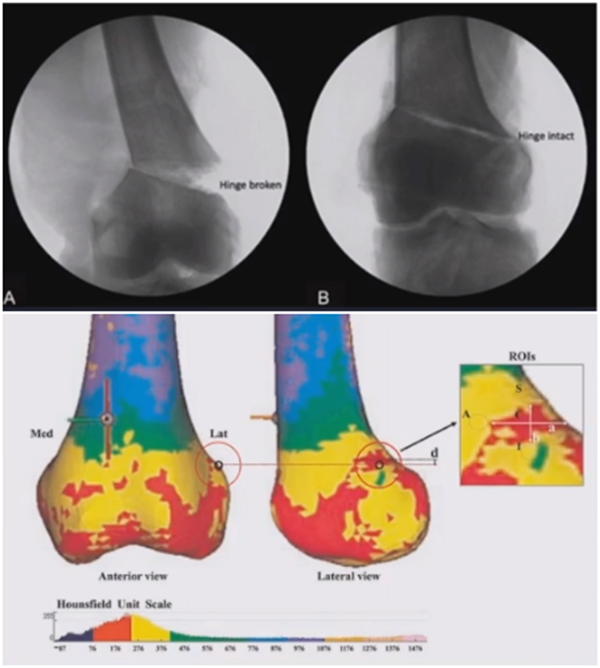

(1)合页骨折

对于术中出现的合页骨折,此时还有一定的稳定性,可以调整力线固定以后,由前外向后内打一根防旋螺钉,这样仍然是比较稳定,术后康复计划与正常一样。

对于术中合页骨折,但非常不稳定、无法控制力线的情况,可以由外侧向股骨外髁打入一枚2.0的克氏针,因为克氏针具有一定弹性,相当于重建合页临时稳定性,在此基础上再去调整力线,做固定。

术后做植骨,早活动、晚负重,避免做扭转活动。

晚期出现的合页骨折,此时力线已经改变,只能进行翻修。

病例,X患者,女,双侧外翻膝,行双侧DFO。

术后6周摔伤,一侧出现膝内翻。

影像学检查显示左侧出现合页断裂。

进行翻修,术前力线显示内翻。

术中发现螺钉松动,截骨端出现坎插迹象。

近端螺钉松开,调整力线,重新固定后,在外侧加小钢板抗旋。

术后10周复查,力线较好。